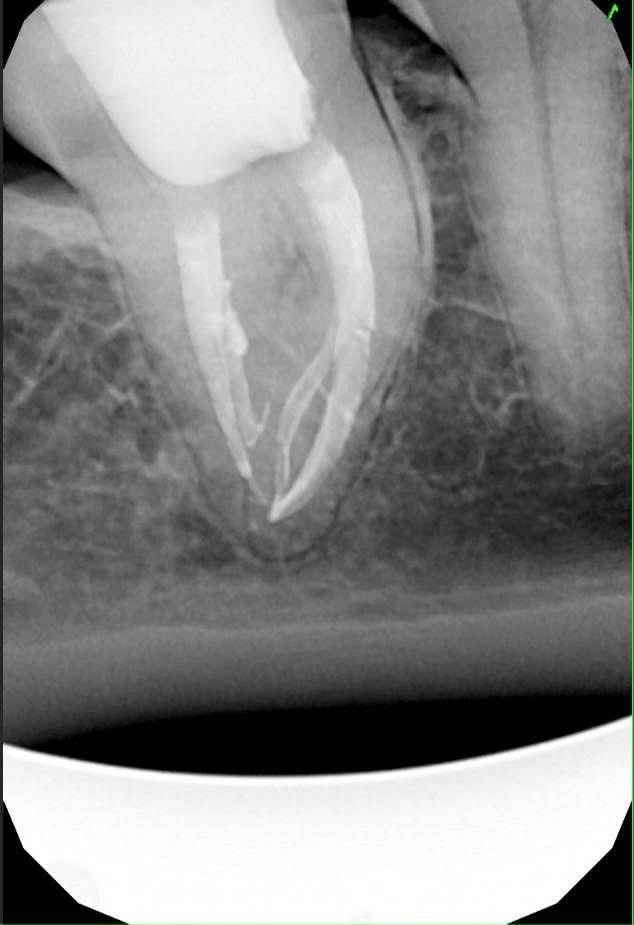

Гарриевич Опубликовано 31 января Автор Поделиться Опубликовано 31 января Когда в твоем кресле оказывается пациент с редким заболеванием «стоматолог-терапевт» работать всегда… легче. Именно! Потому что ты на 100% уверен, что этот человек понимает разницу между «гарантия» и «прогноз», а он на 100% уверен, что ты тот кто ему нужен. Зуб 4.7 со сложной анатомией, ступенькой в мезиальной системе, двойным изгибом, пропущенным каналом и апикальным периодонтитом. Реколл 1 год И сам осмотр через 1 год 4 1 1 Ссылка на комментарий